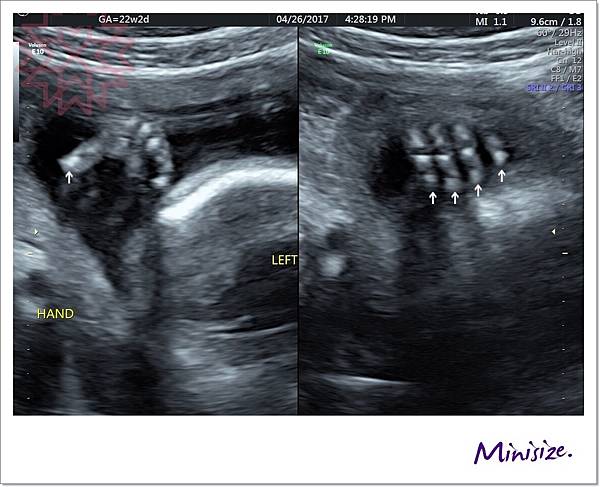

手

剛好我的寶寶手手有摺起來

技術師用兩種不同角度拍照

檢查時會細數1、2、3、4、5 五支手指頭

下兩張左圖都是大拇指 右圖是其餘四指

左手